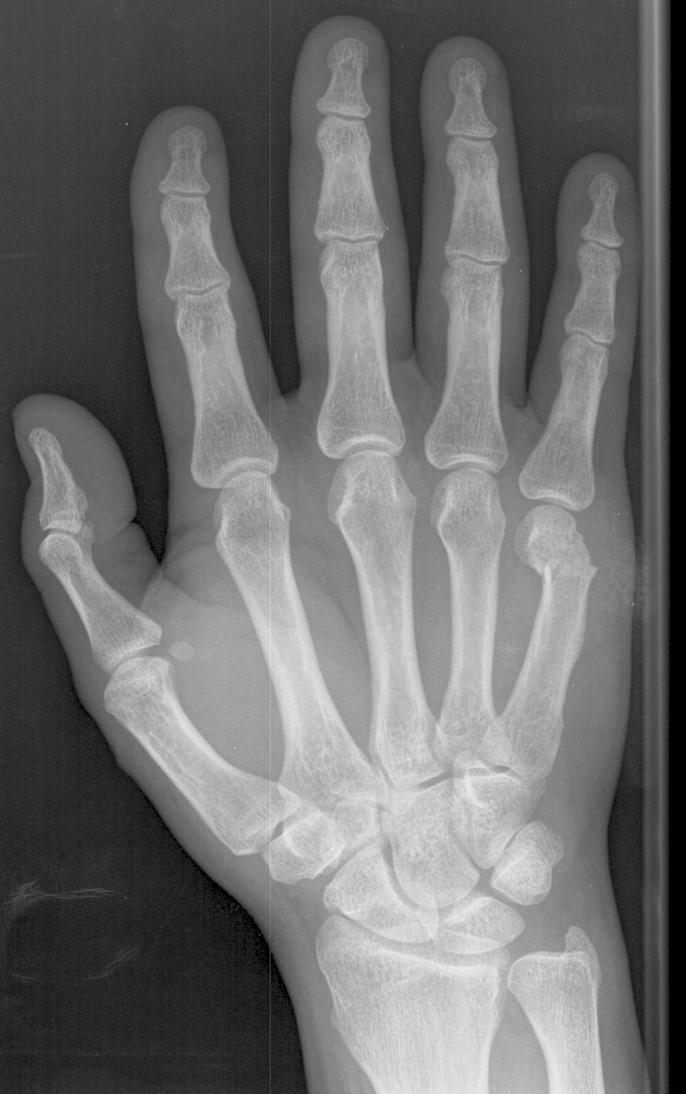

Knuckle Anatomy Anatomical Charts & Posters